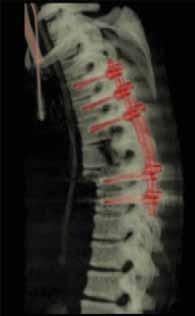

Rycina 70.5.

Rycina 70.6.

Rycina 70.7.

Rycina 70.8.